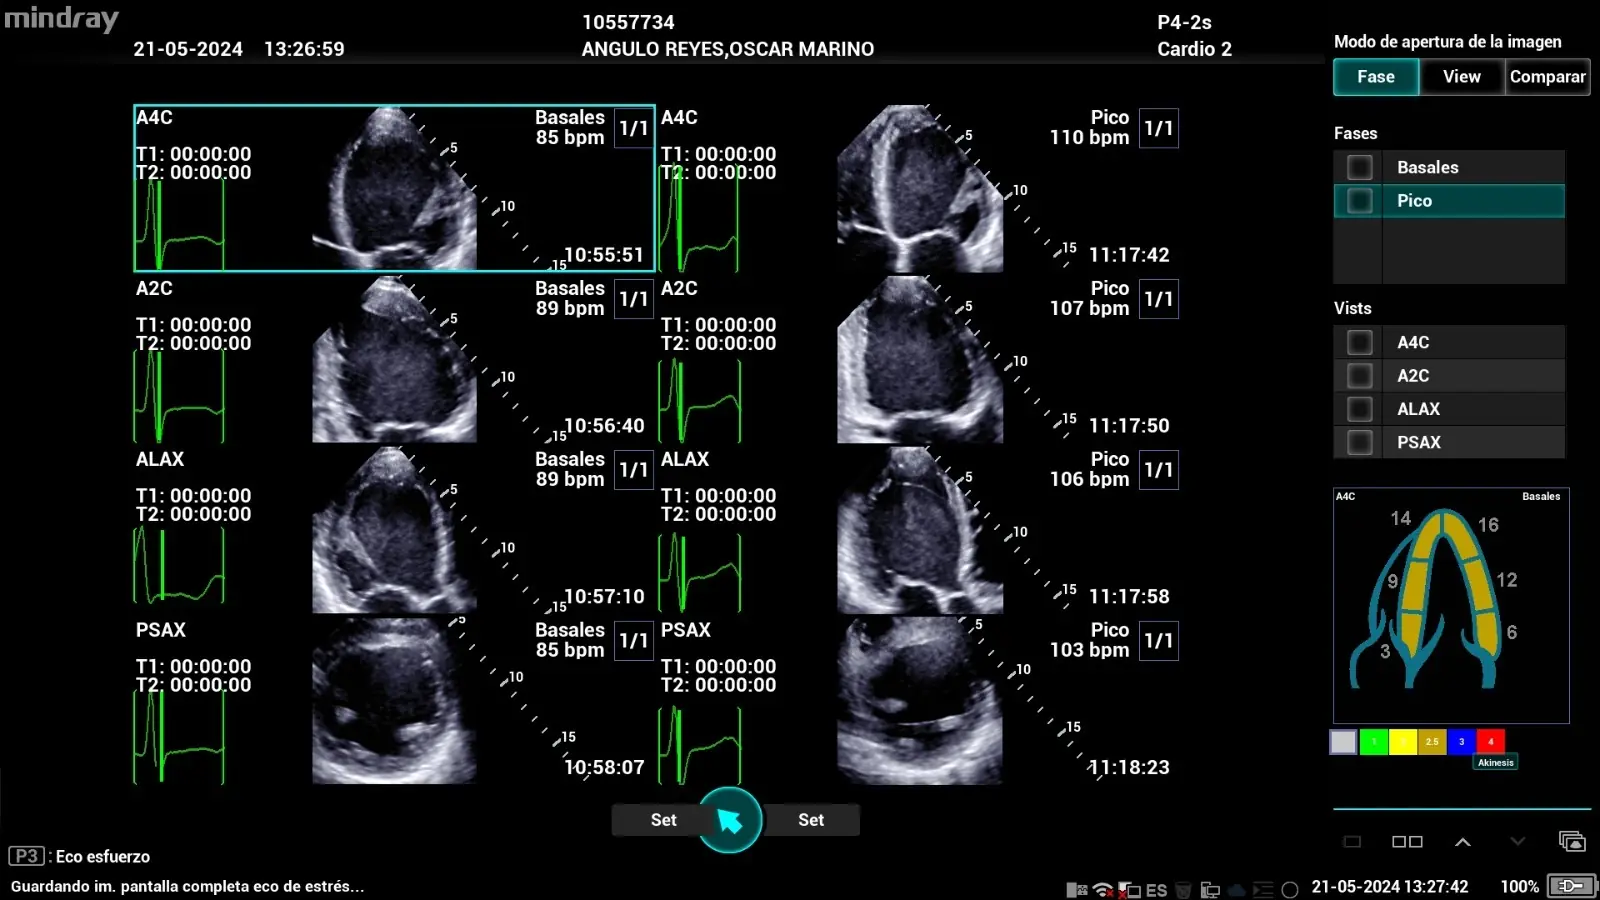

- Doppler color: representa el flujo sanguíneo en tiempo real mediante un mapeo codificado por colores, facilitando la identificación visual de turbulencias, flujos retrógrados o alteraciones hemodinámicas. Es clave en estudios de válvulas y comunicación interventricular.

- Doppler tisular (Tissue Doppler Imaging): analiza la velocidad de desplazamiento del miocardio en vez del flujo sanguíneo, lo que resulta útil para evaluar la función diastólica y detectar disfunción ventricular temprana.

Detección temprana de alteraciones hemodinámicas

Como hemos mencionado, uno de los mayores aportes de esta tecnología es su utilidad en el seguimiento de pacientes con factores de riesgo cardiovascular, ya que permite diagnosticar disfunciones valvulares, trastornos del llenado ventricular o signos de insuficiencia cardíaca incipiente con gran precisión. Asimismo, su integración con modalidades como el doppler tisular mejora la caracterización funcional del miocardio, favoreciendo la intervención precoz.

Entre las alteraciones hemodinámicas que pueden detectarse en estados iniciales mediante los equipos eco doppler se incluyen:

- Disfunción diastólica del ventrículo izquierdo: mediante el análisis del flujo transmitral, la relación E/A y el Doppler tisular (E’), se identifican patrones de relajación anormal antes de que haya síntomas.